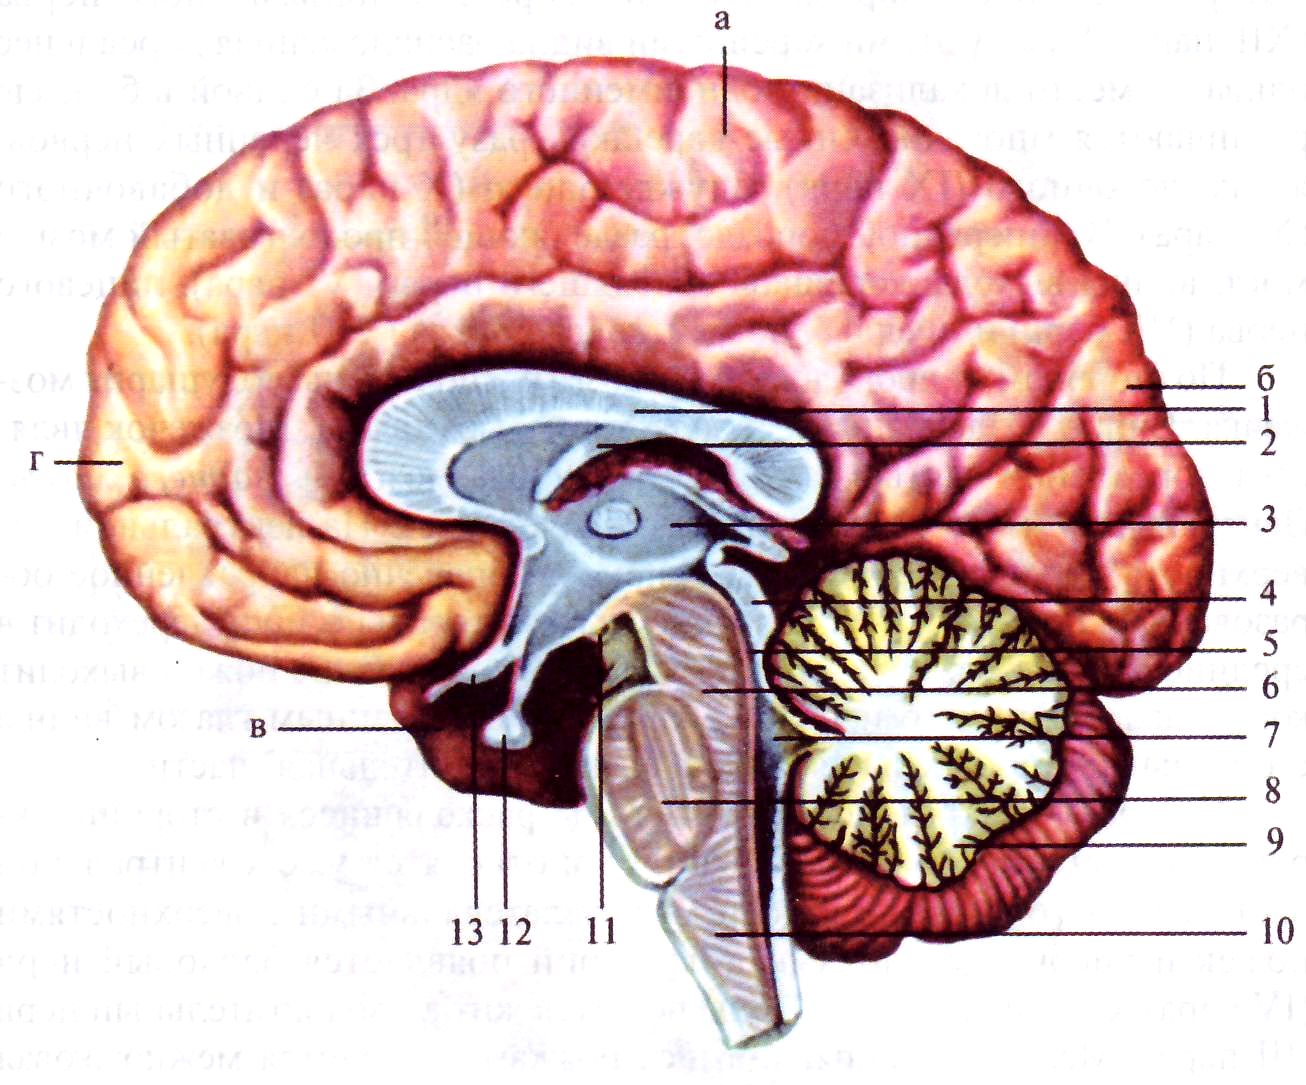

Легкие рисунки головного мозга: Пошаговые инструкции

Раздел: Житейские мотивы